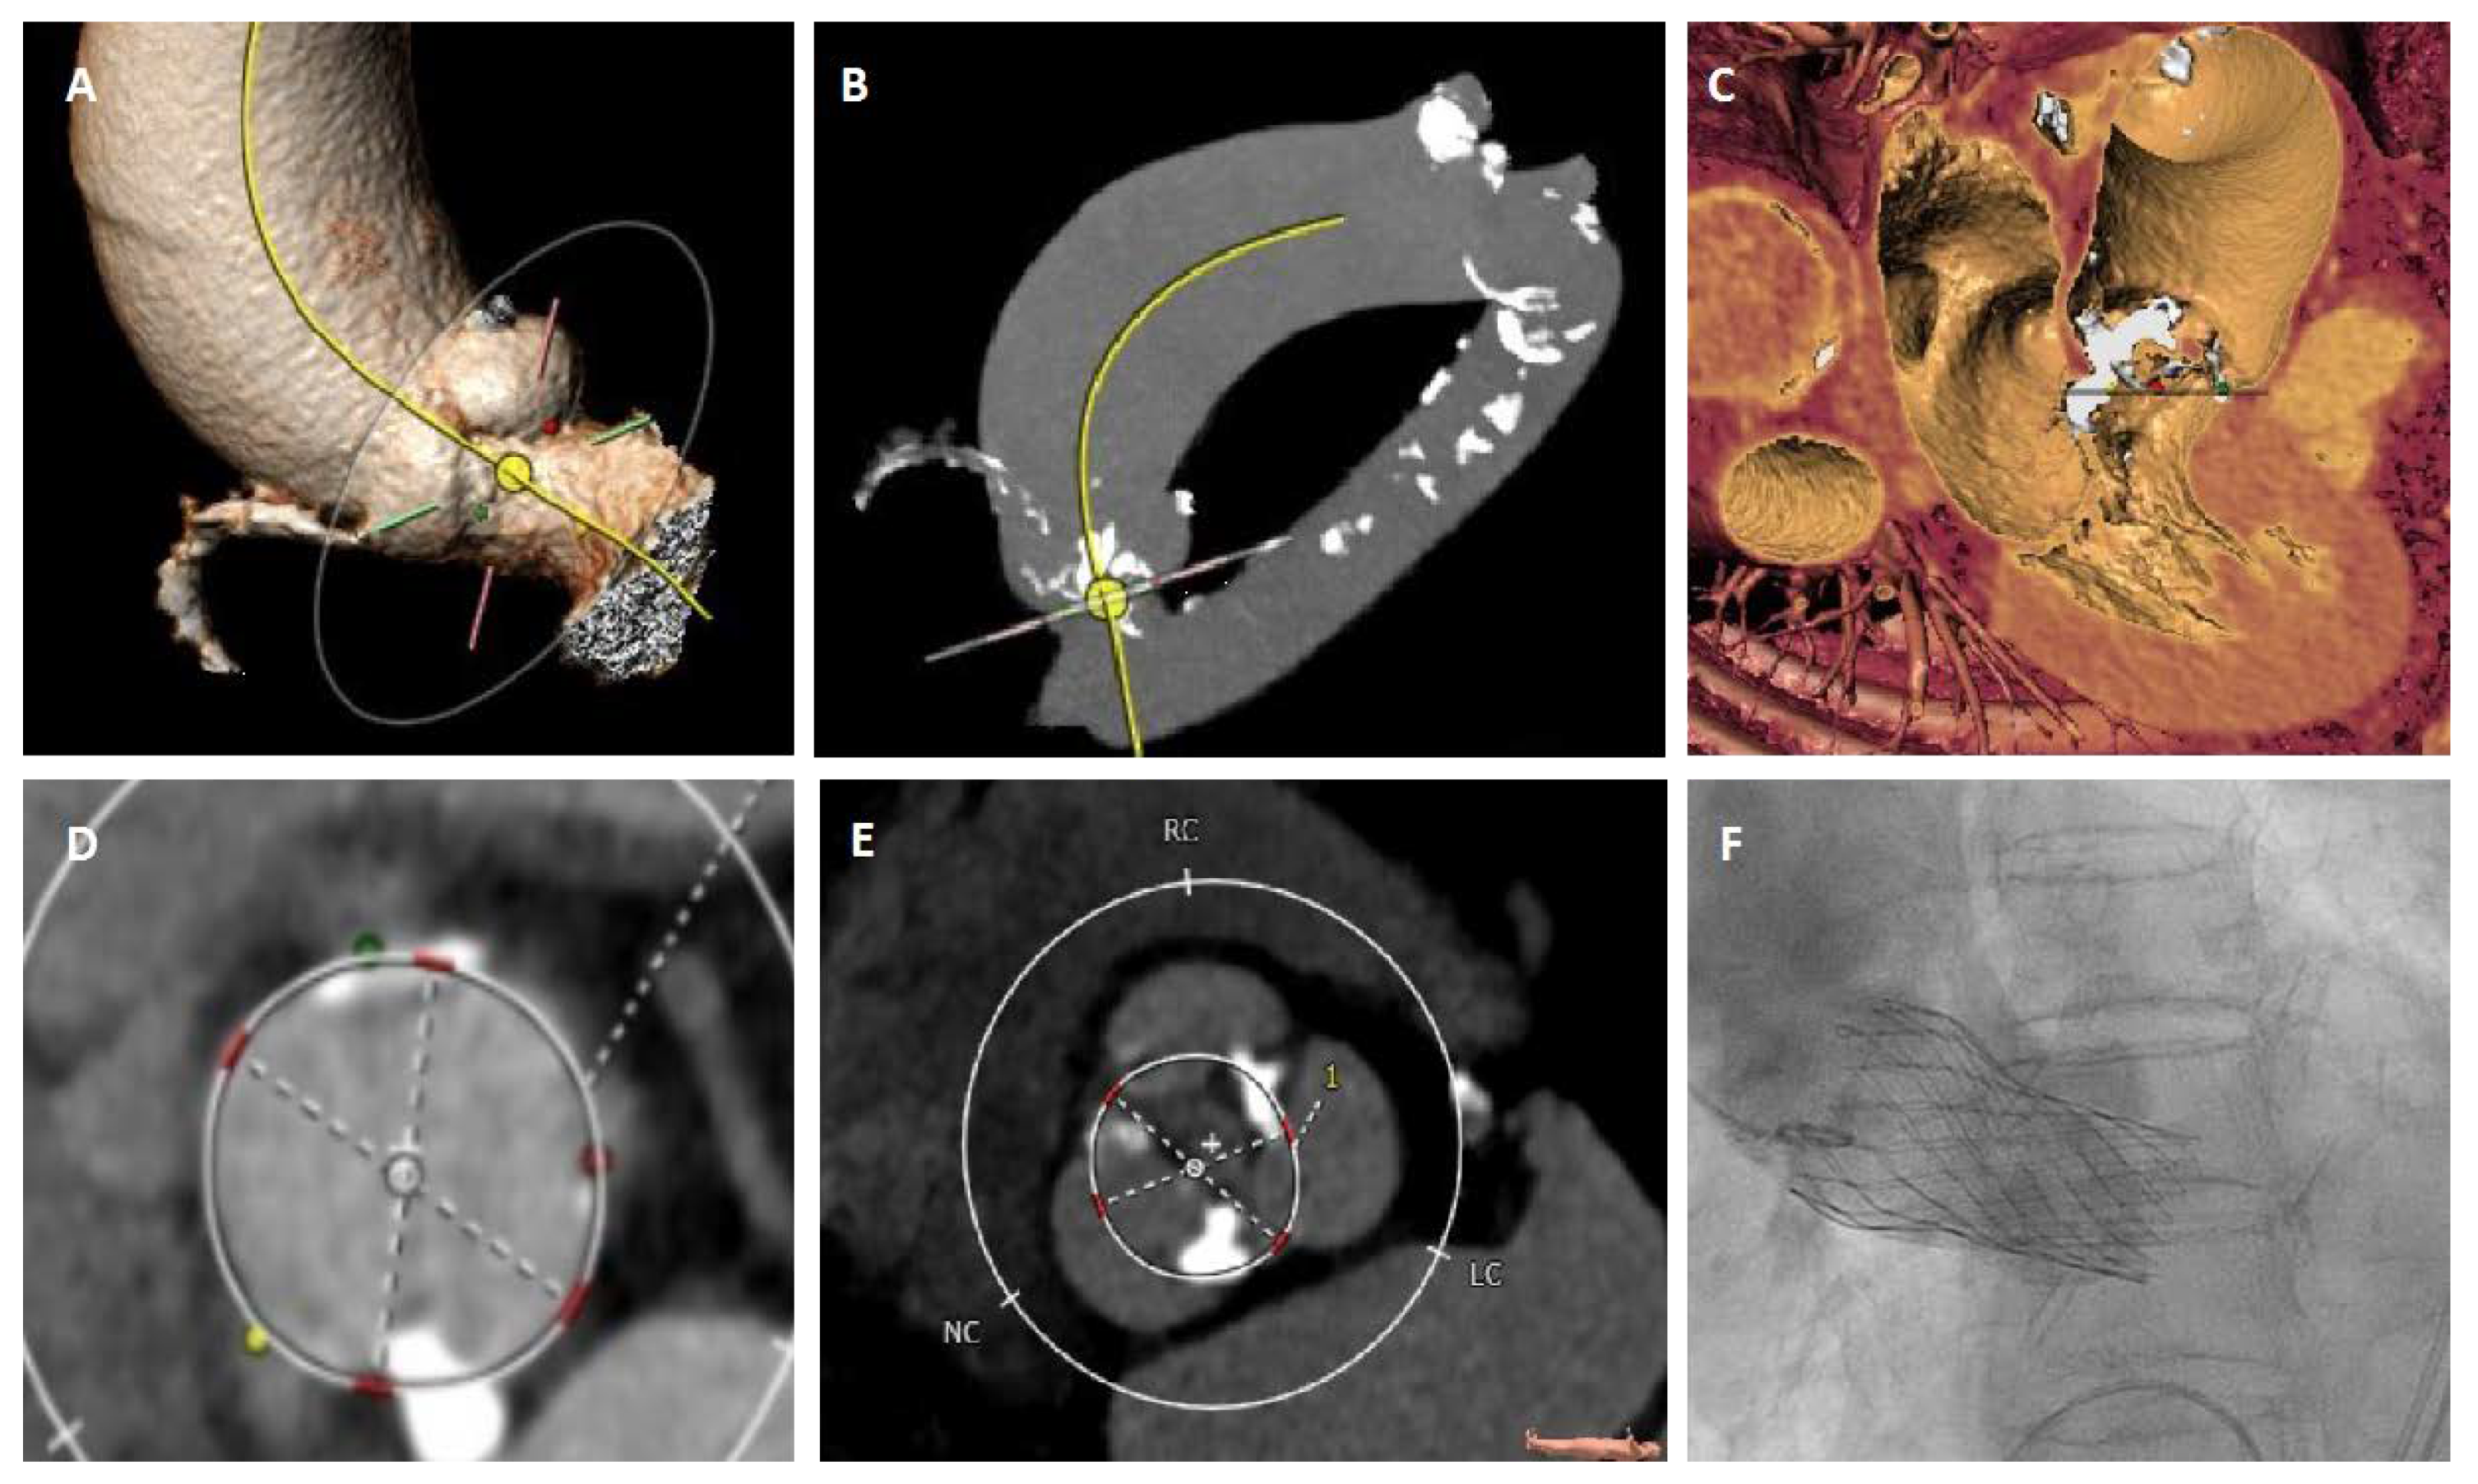

3.2. Transcatheter Aortic Valve Replacement (TAVR)